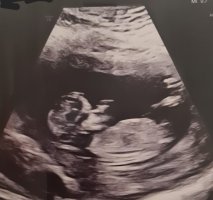

Denne er veldig enkel, men legger ut likevel så får folk gjette om de vilJeg vet jo hva det er

13+4

Ser jentete ut, men jeg klarer ikke se hvor blæra er. Hvor langt er du påvei?

13 +1 når ultralyden ble tattSer jentete ut, men jeg klarer ikke se hvor blæra er. Hvor langt er du påvei?

Da tenker jeg det burde vært stacking eller stått mer opp om det var en gutt. Så tenker jente13 +1 når ultralyden ble tatt![]()